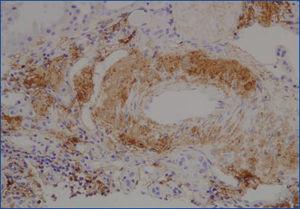

Se decide realizar una biopsia renal, que muestra 26 glomérulos, de los cuales 17 están esclerosados. En algunos de los glomérulos no esclerosados se observan muy focales depósitos nodulares de material hialino eosinófilo, acelular y débilmente ácido peryodico (PAS+) más frecuente en el polo vascular (figura 1), material que se observa también y en mayor cantidad en intersticio y en pared de arterias y arteriolas (figura 2). Este material se tiñe con la técnica de rojo congo (figura 3 y figura 4), tinción que desaparece tras el tratamiento con permanganato, y muestra birrefringencia verde manzana con luz polarizada. Con técnicas de inmunohistoquímica, el material acelular muestra tinción con amiloide A (figura 5). Se observa además una fibrosis intersticial y atrofia tubular moderadas (20 %). Con estos datos histológicos, se realiza el diagnóstico de amiloidosis renal secundaria (AA) con afectación glomerular, vascular e intersticial.

La amiloidosis se define por la acumulación extracelular de una proteína que muestra positividad con la técnica de rojo congo, birrefringencia verde manzana con luz polarizada y que en el estudio ultraestructural forma fibrillas de 10 nm no ramificadas y dispuestas de forma aleatoria. El material amiloide puede estar compuesto por una variedad de diferentes polipéptidos, que incluye cadenas ligeras de inmunoglobulinas (AL amiloide), cadenas pesadas (AH amiloide) proteína A amiloide (AA amiloide), beta-2-microglobulina, transtiretina, procalcitonina, beta-amiloide proteína, cistatina C, etc. La amiloidosis AA o secundaria se asocia a diferentes tipos de entidades, como enfermedades autoinmunes crónicas y enfermedades infecciosas crónicas, pero también aparece como complicación de la fiebre mediterránea familiar y en los CAPS. Independientemente de la causa, el amiloide presenta siempre las mismas características histológicas y ultraestructurales6. En nuestro caso, la biopsia renal muestra las características típicas de una amiloidosis secundaria tipo AA con depósitos de material amiloide preferentemente a nivel vascular, pero también en glomérulos e intersticio, con birrefringencia verde manzana con luz polarizada y que se pierde tras el tratamiento con permanganato. La positividad con inmunohistoquímica para amiloide A confirma el diagnóstico.

Figura 4. Depósitos de material amiloide en arterias con técnica de rojo congo.